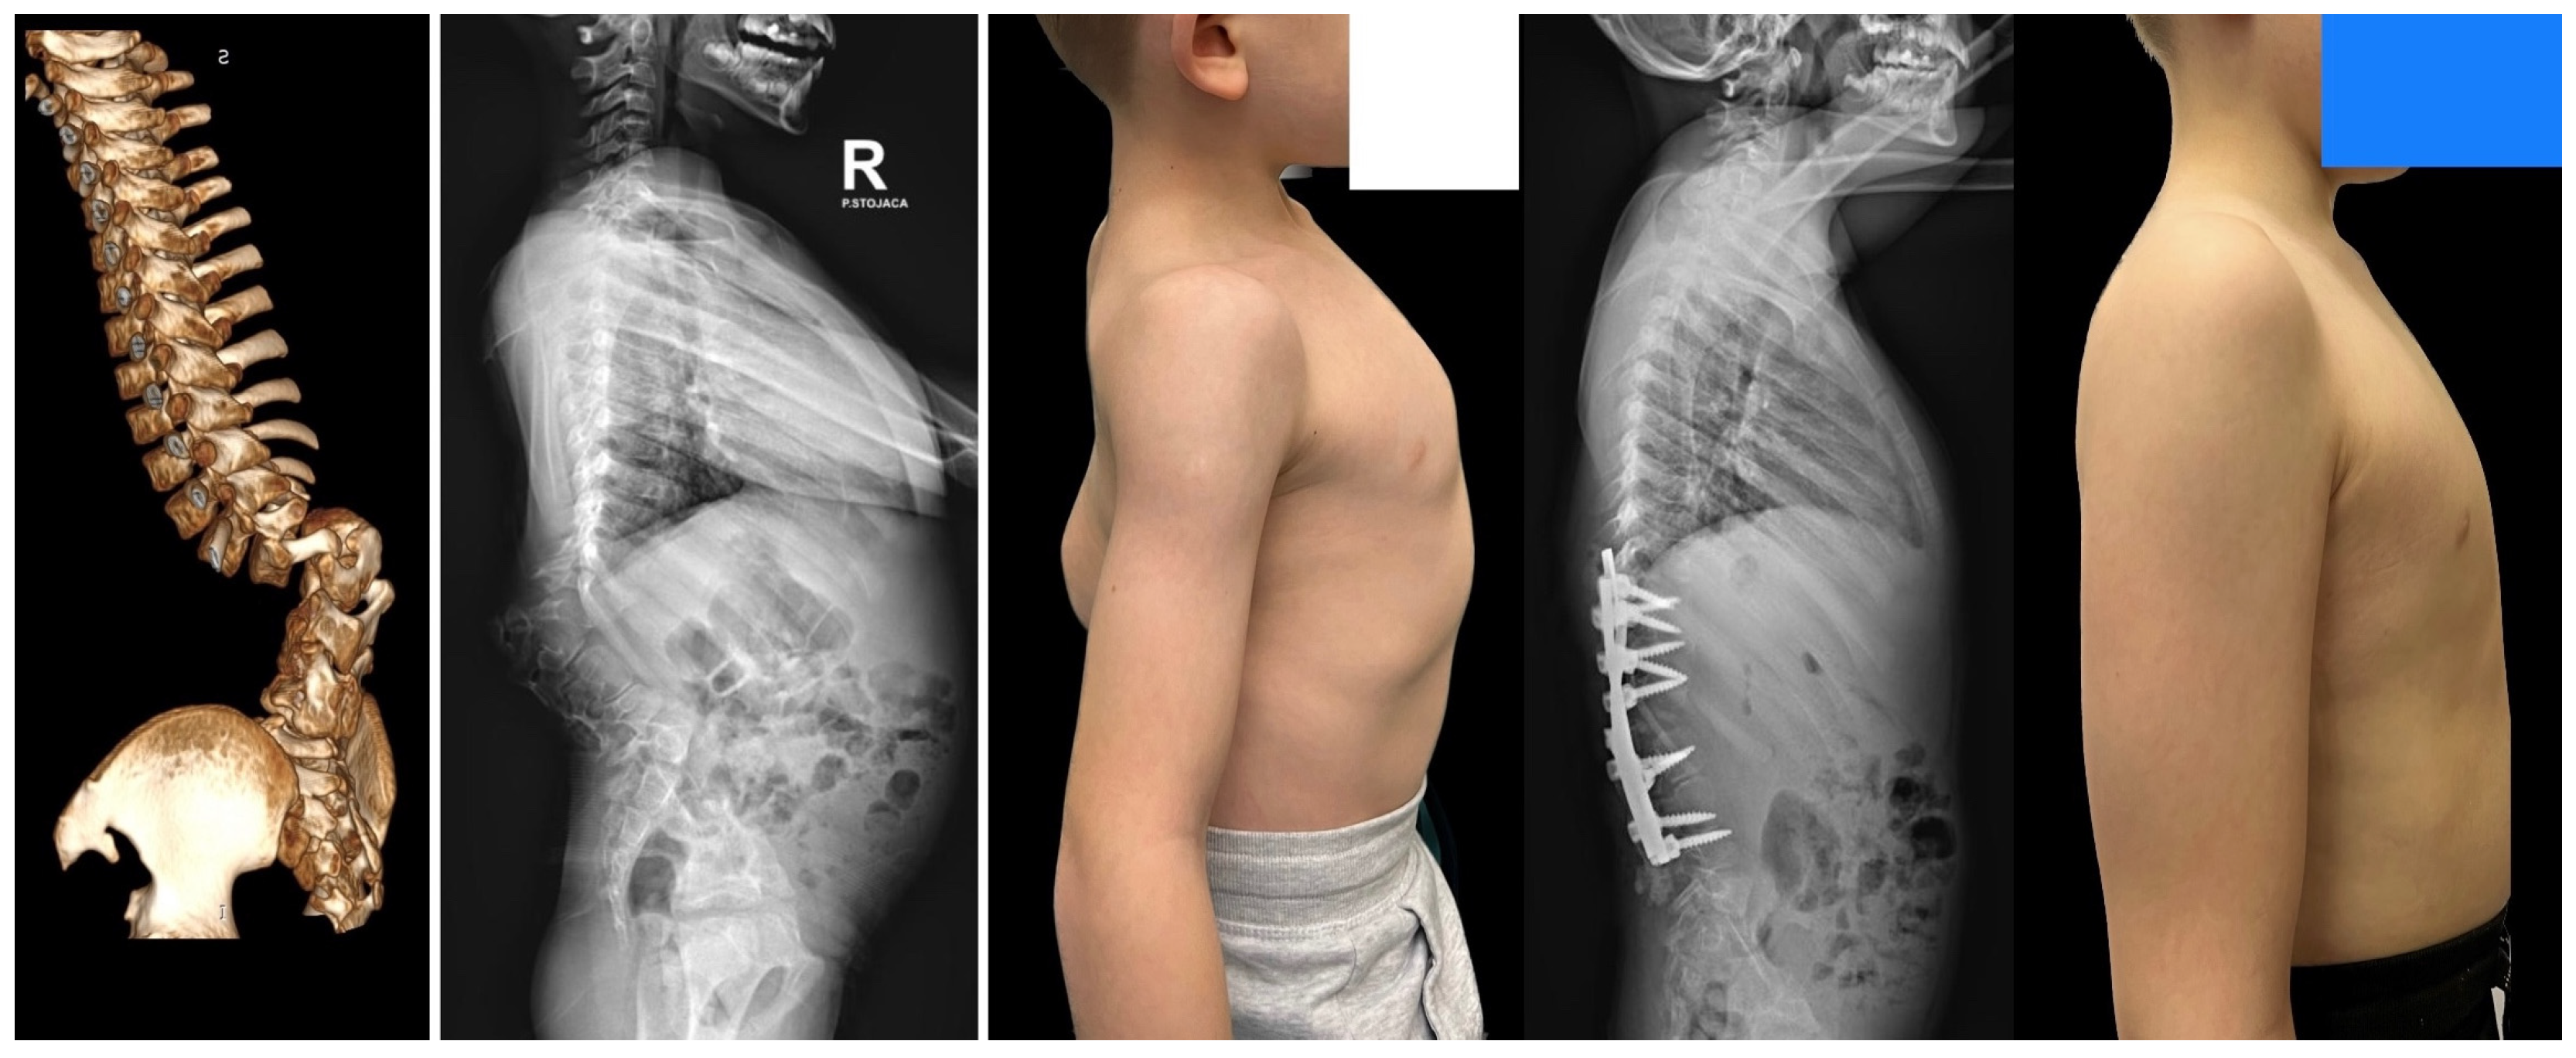

8. Complications and Risk Management

- Grabala, P.; Fani, N.; Gregorczyk, J.; Grabala, M. Posterior-only T11 vertebral column resection for pediatric congenital kyphosis surgical correction. Medicina 2024, 60, 897. [Google Scholar] [CrossRef] [PubMed]

- Gupta, M.C. Vertebral column resection for severe kyphosis. Neurosurg. Focus. Video 2020, 2, V10. [Google Scholar] [CrossRef]